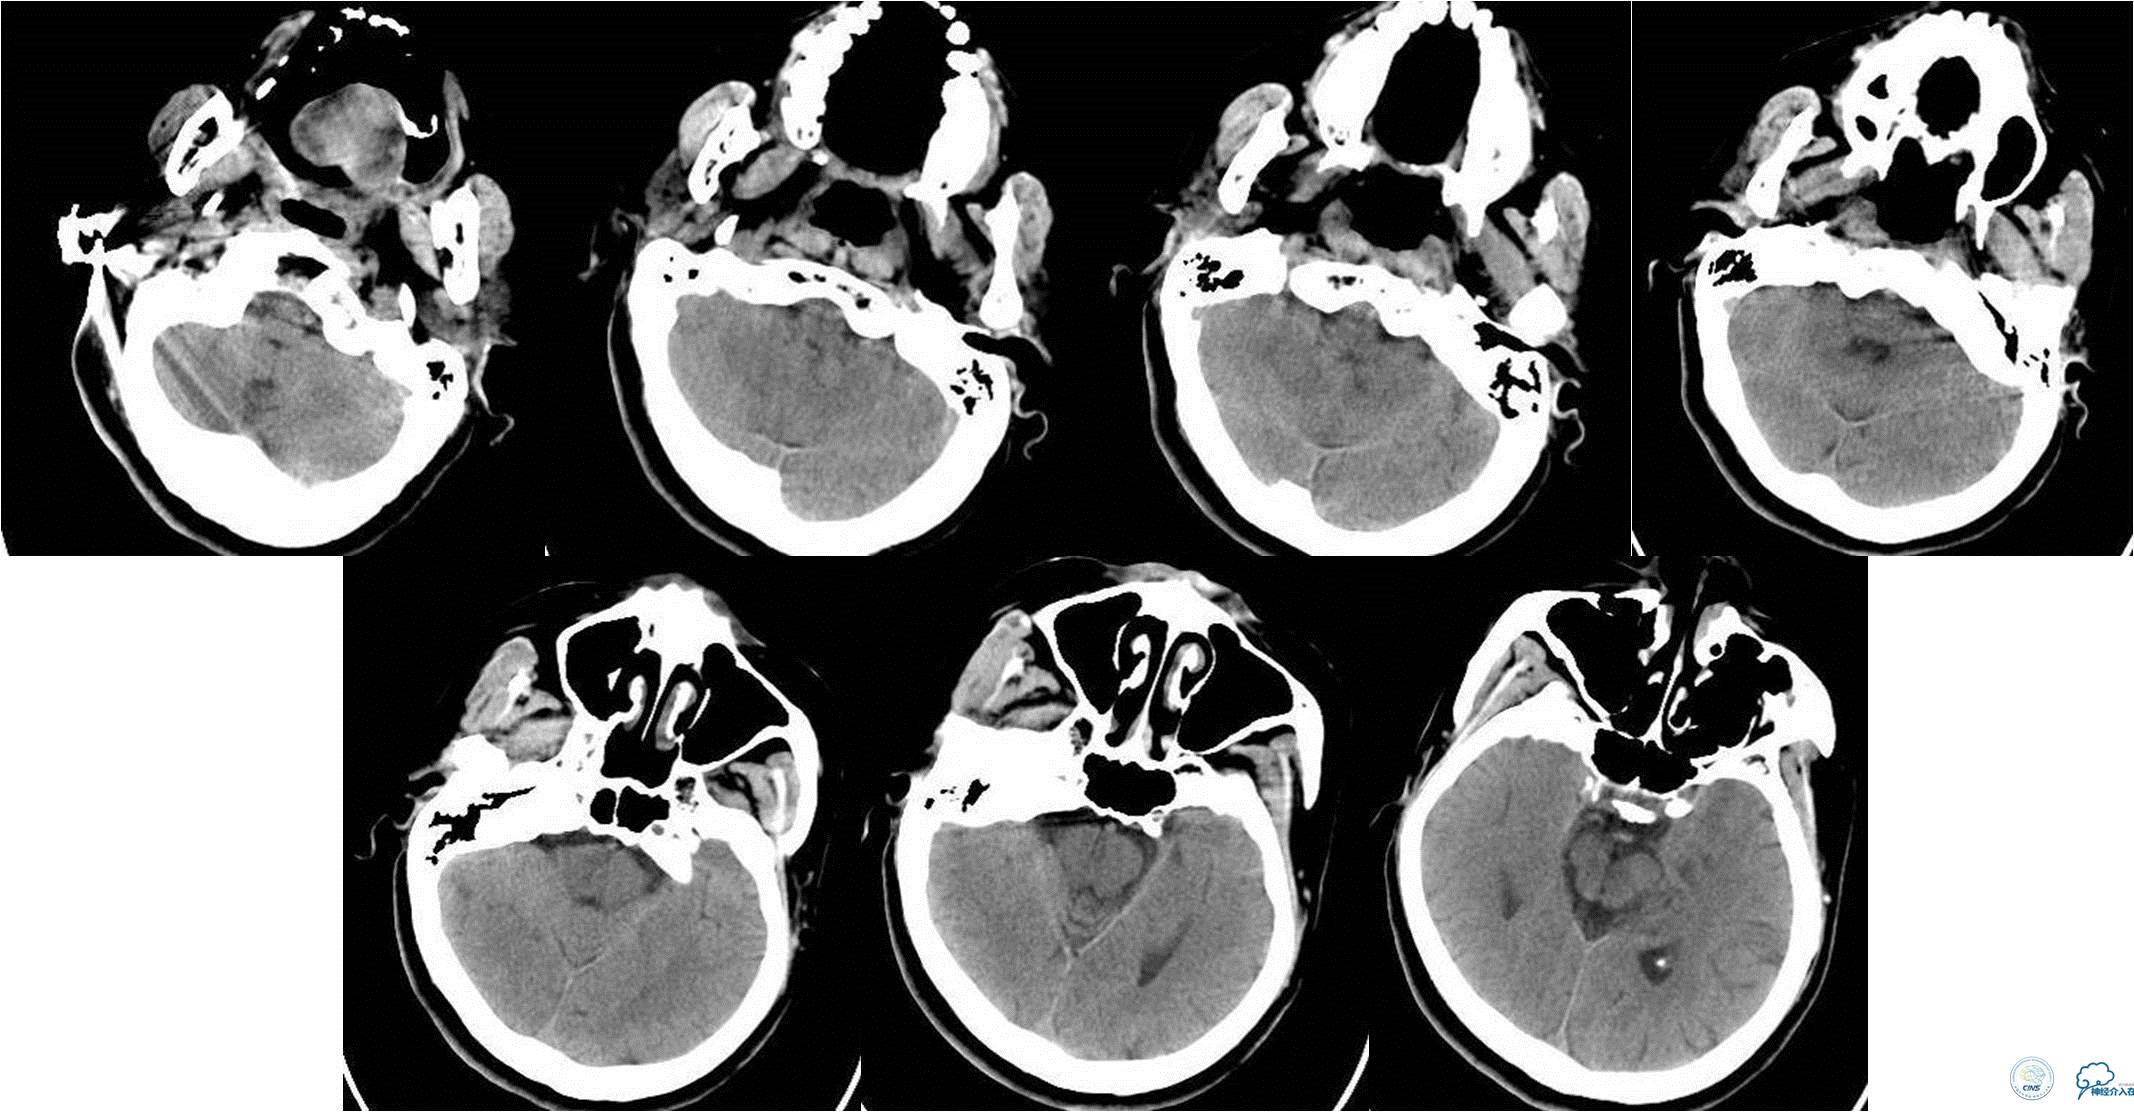

入院时急查颅脑CT(发病2.5小时)